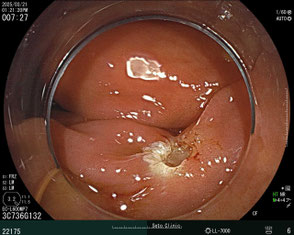

ポリープ治療の事例

ワイヤーで切除して止血を確認した